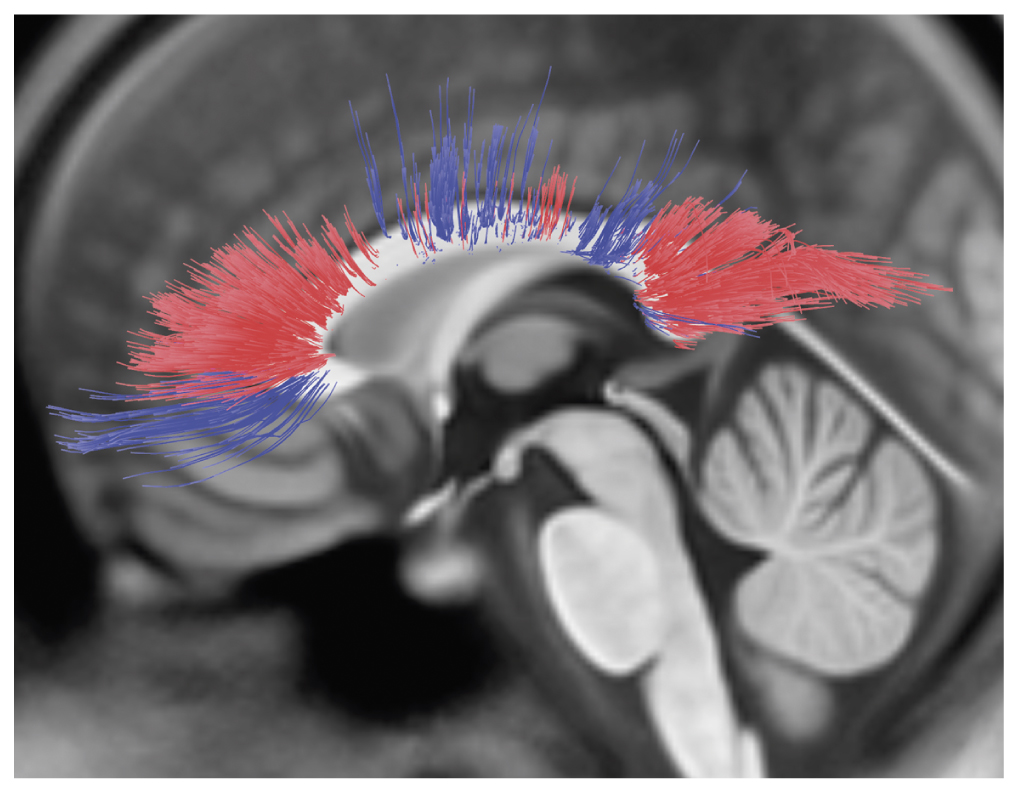

При наложении полученных результатов в одном объеме заметно перекрытие некоторых выявленных проводящих путей белого вещества, в то же время выявляются и различия: результаты представлены на рис. 3.

Рис. 3. Трехмерные реконструкции головного мозга и проводящих путей с наибольшим значением показателя количественной анизотропии (QA) у мужчин (красный) и женщин (синий). / Fig. 3. 3D reconstructions of the brain and pathways with the highest index of quantitative anisotropy (QA), in men (red) and women (blue).

У мужчин преобладали проводящие пути недоминантного аркуатного пучка справа (большинство испытуемых правши), тракты поясной извилины, передние отделы корково-стриарного пути, кортикоретикулярный путь справа, а также часть верхнего продольного пучка слева и справа.

У женщин наблюдалось преобладание проводящих путей передней спайки, части тракта поясной извилины в парагиппокампальной области слева, кортикопонтинового пути в лобной и затылочных долях справа, а также кортикопонтинного пути теменной доли с двух сторон, пирамидного тракта с двух сторон, заднего и верхнего отделов корково-стриарного пути, дентаторуброталамического тракта с двух сторон, самой наружной капсулы слева, проводящих путей свода с двух сторон, лобного косого тракта слева, нижнего продольного пучка слева, медиальной петли справа, зрительной лучистости слева, верхнего и переднего таламо-коркового пути и заднего таламо-коркового пути слева.

Помимо этого, в рамках одного анатомического тракта наблюдалось преобладание различных его пучков у обоих полов: доминантный аркуатный тракт слева (большинство испытуемых правши), проводящих путей мозолистого тела, нижнего лобно-затылочного пучка, нижнего и верхнего продольного пучка справа.